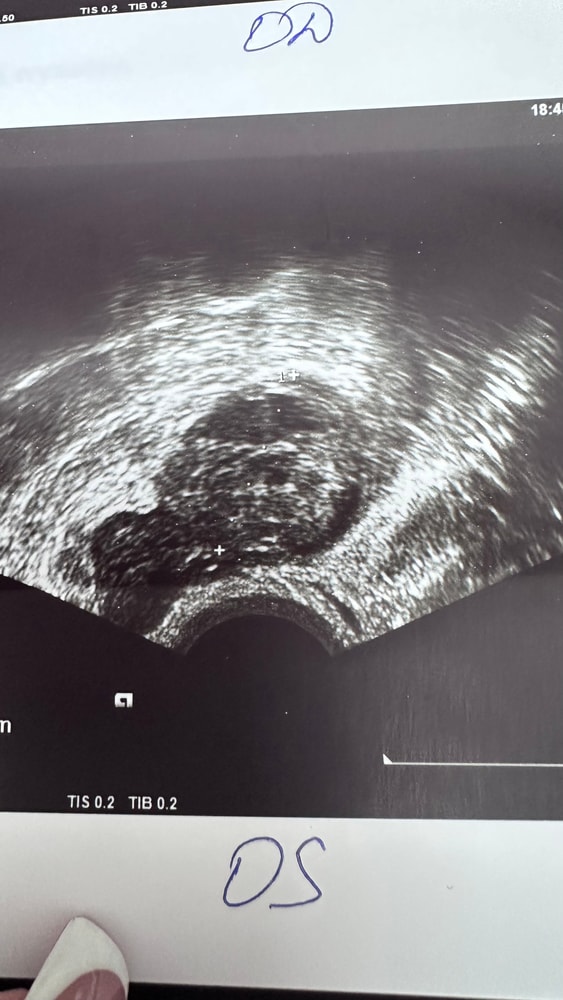

Собрала тесты с цикла в коробку, как всегда😩

Вышла из дисперсии очередной неудачи…заказала тесты, уже в пути…ведь тестов много не бывает, уж я то знаю, спустя столько л

Вчера утро:

Сегодня день:

Что-то я понять не могу, свой организм вместе с тестами на овуляцию.

понедельник вечер:

Вторник 7 утра:

Тестик на овуляцию ярчает) я радуюсь как ребенок😂 овуляция с СПКЯ, большая редкость. Последняя была в январе (стимулированная), а предпоследняя в мае 2024 года. 20 д.ц и счаст